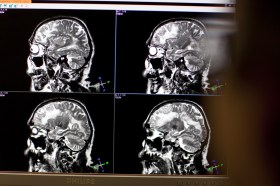

The part of the brain which controls emotional response alters due to trauma Keystone

A Lausanne-based research team has found the first concrete evidence of a long-sought-after biological link between trauma experienced in childhood and an inability to control violent behaviour later in life.

Carmen Sandi, who leads the research team in the Laboratory of Behavioural Genetics at the Federal Institute of Technology in Lausanne (EPFL), says a link between a traumatic childhood and violent tendencies in adulthood has long been examined and accepted from a psychological perspective.  However, her team found for the first time physical evidence of the brain’s neurobiological structure being altered by traumatic experiences during the formative years.

The link is particularly demonstrated through the MAOA gene, located in the prefrontal cortex region of the brain. In male rats that experienced violence or trauma as youngsters, the gene’s expression changed long-term to make the rats unable to inhibit violent impulses and therefore show more aggressive behaviour.